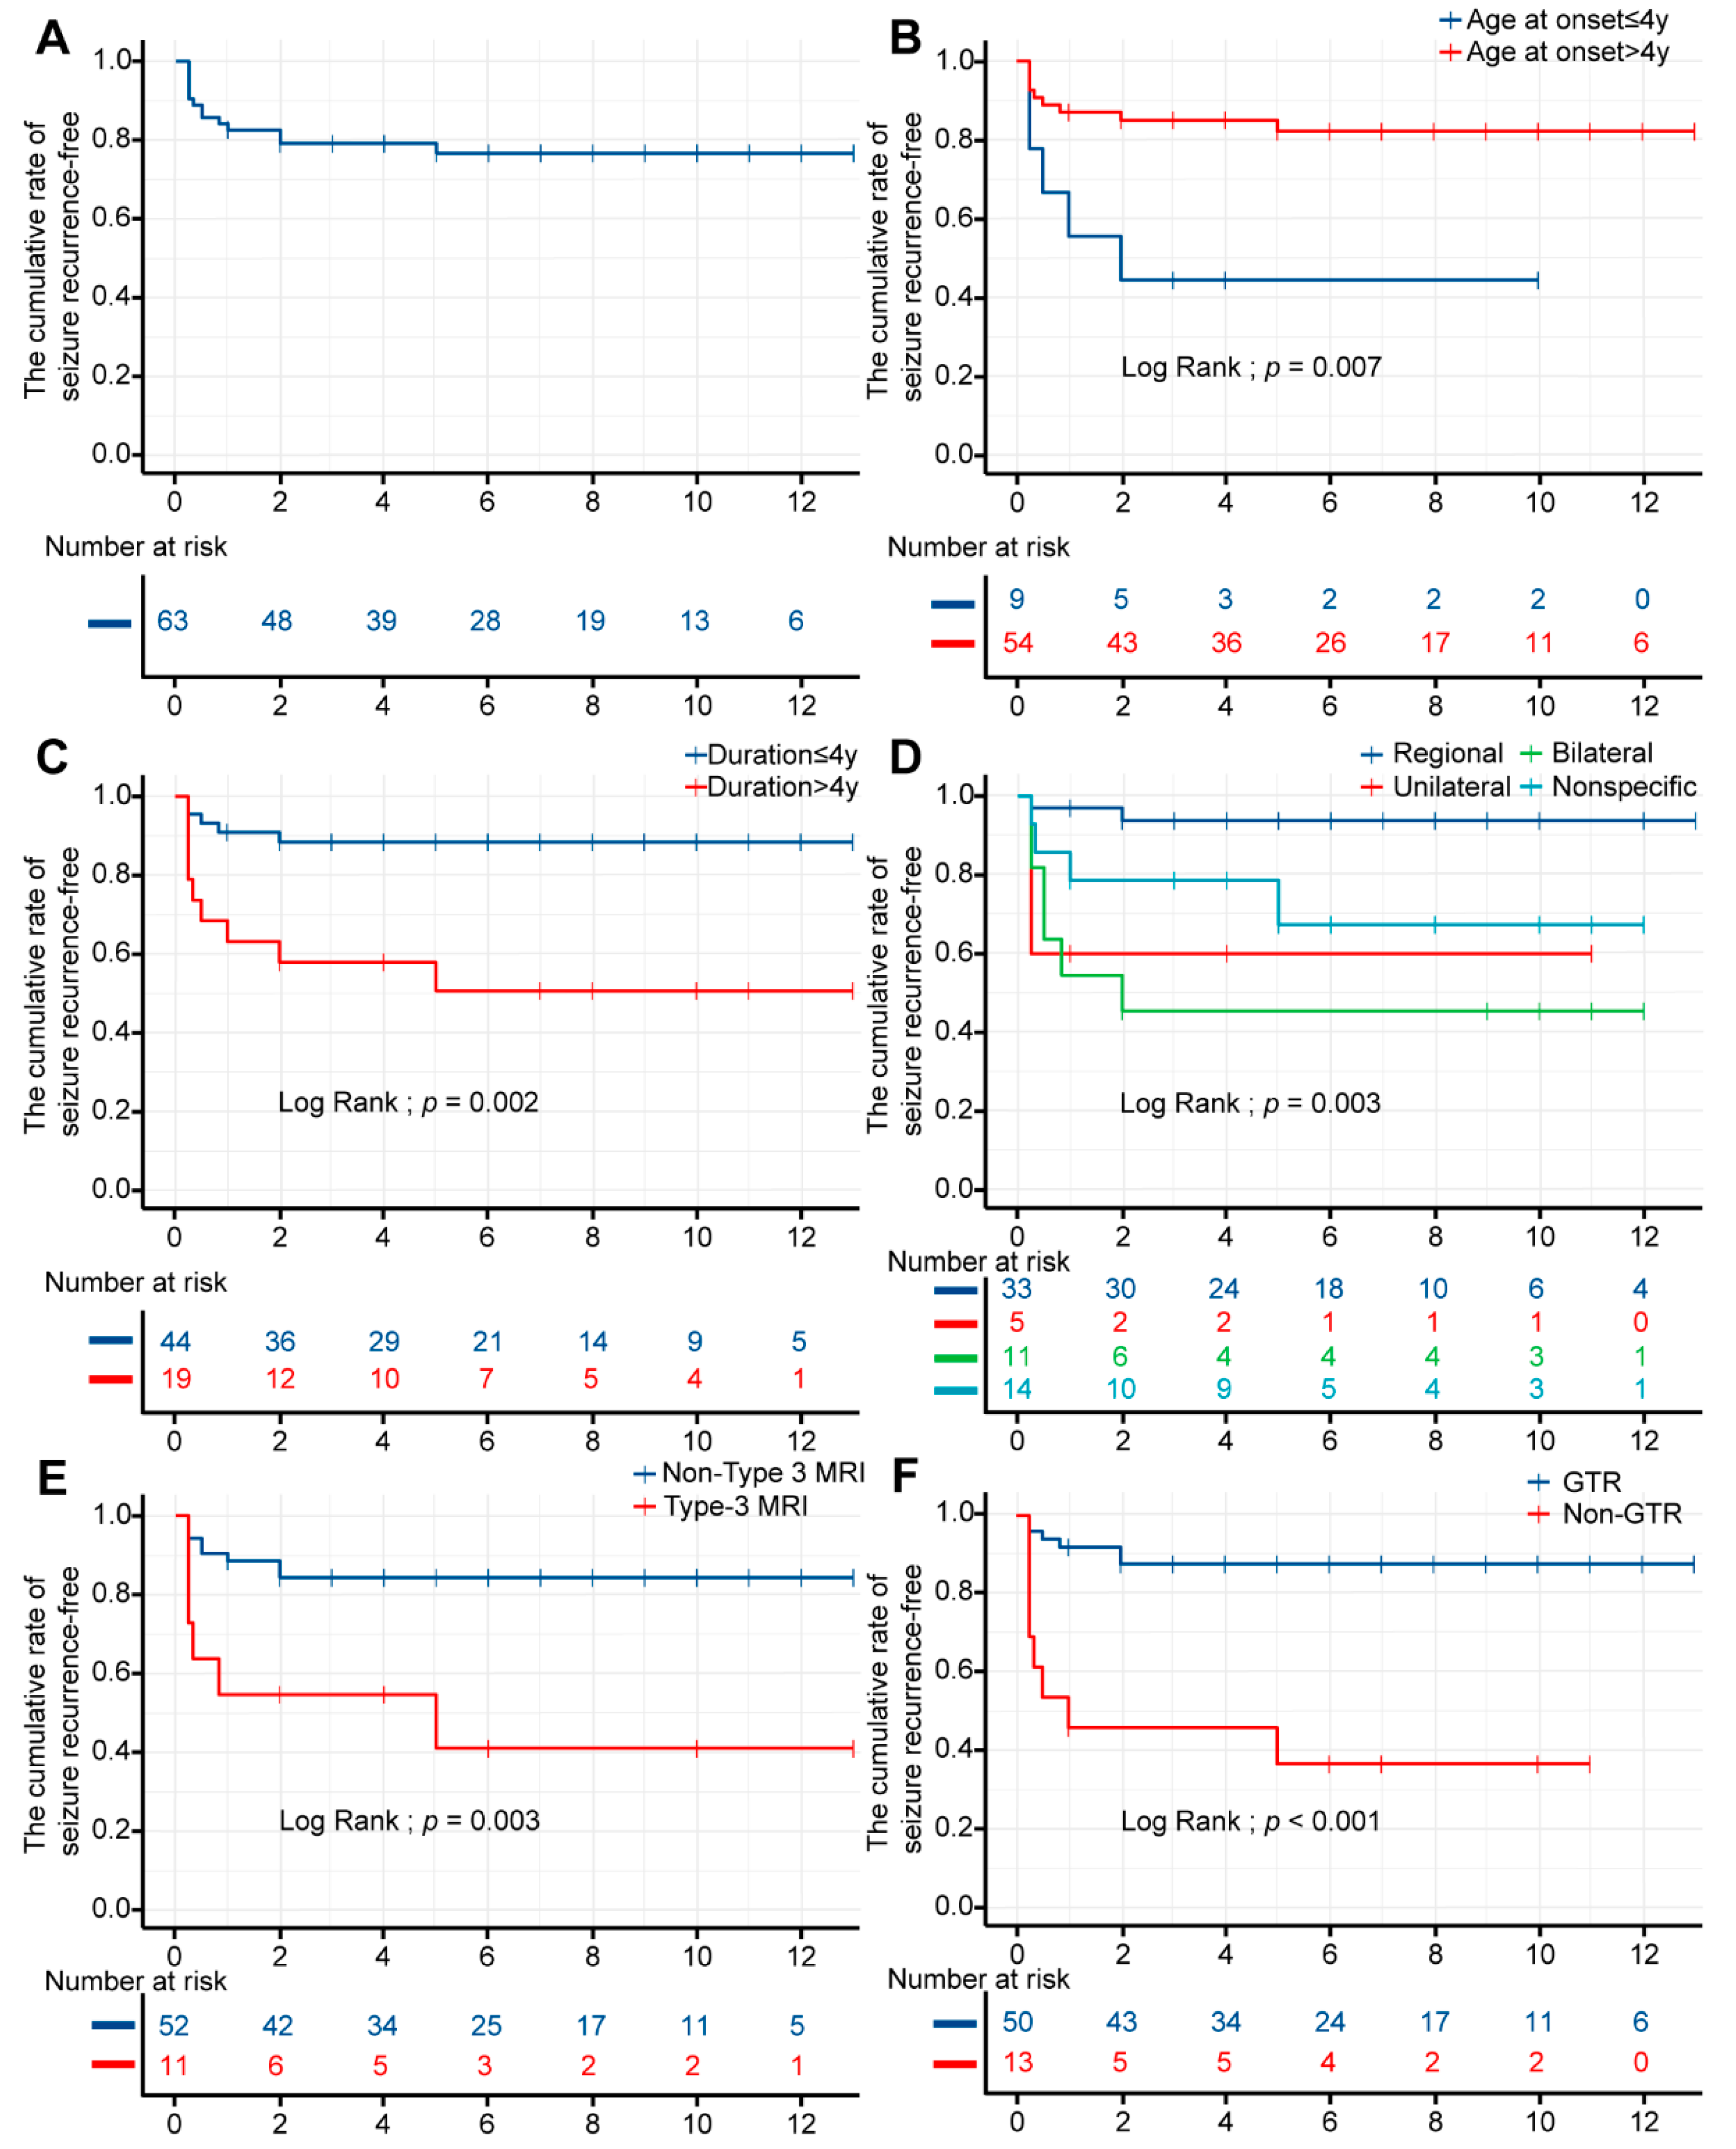

3.5. Univariable Survival Analysis

3.6. Multivariable Cox Regression Analysis

Appendix A

| Time, Years | Cumulative Rate of Seizure Recurrence-Free (%) | Standard Error | 95% CI (%) |

|---|---|---|---|

| 1 | 84.1 | 0.0460 | 75.6–93.7 |

| 2 | 82.5 | 0.0478 | 73.7–92.5 |

| 3 | 79.0 | 0.0518 | 69.5–89.9 |

| 4 | 79.0 | 0.0518 | 69.5–89.9 |

| 5 | 79.0 | 0.0518 | 69.5–89.9 |

| 6 | 76.5 | 0.0561 | 66.2–88.3 |

| 7 | 76.5 | 0.0561 | 66.2–88.3 |

| 8 | 76.5 | 0.0561 | 66.2–88.3 |

| 9 | 76.5 | 0.0561 | 66.2–88.3 |

| 10 | 76.5 | 0.0561 | 66.2–88.3 |

| 11 | 76.5 | 0.0561 | 66.2–88.3 |

| 12 | 76.5 | 0.0561 | 66.2–88.3 |

| 13 | 76.5 | 0.0561 | 66.2–88.3 |